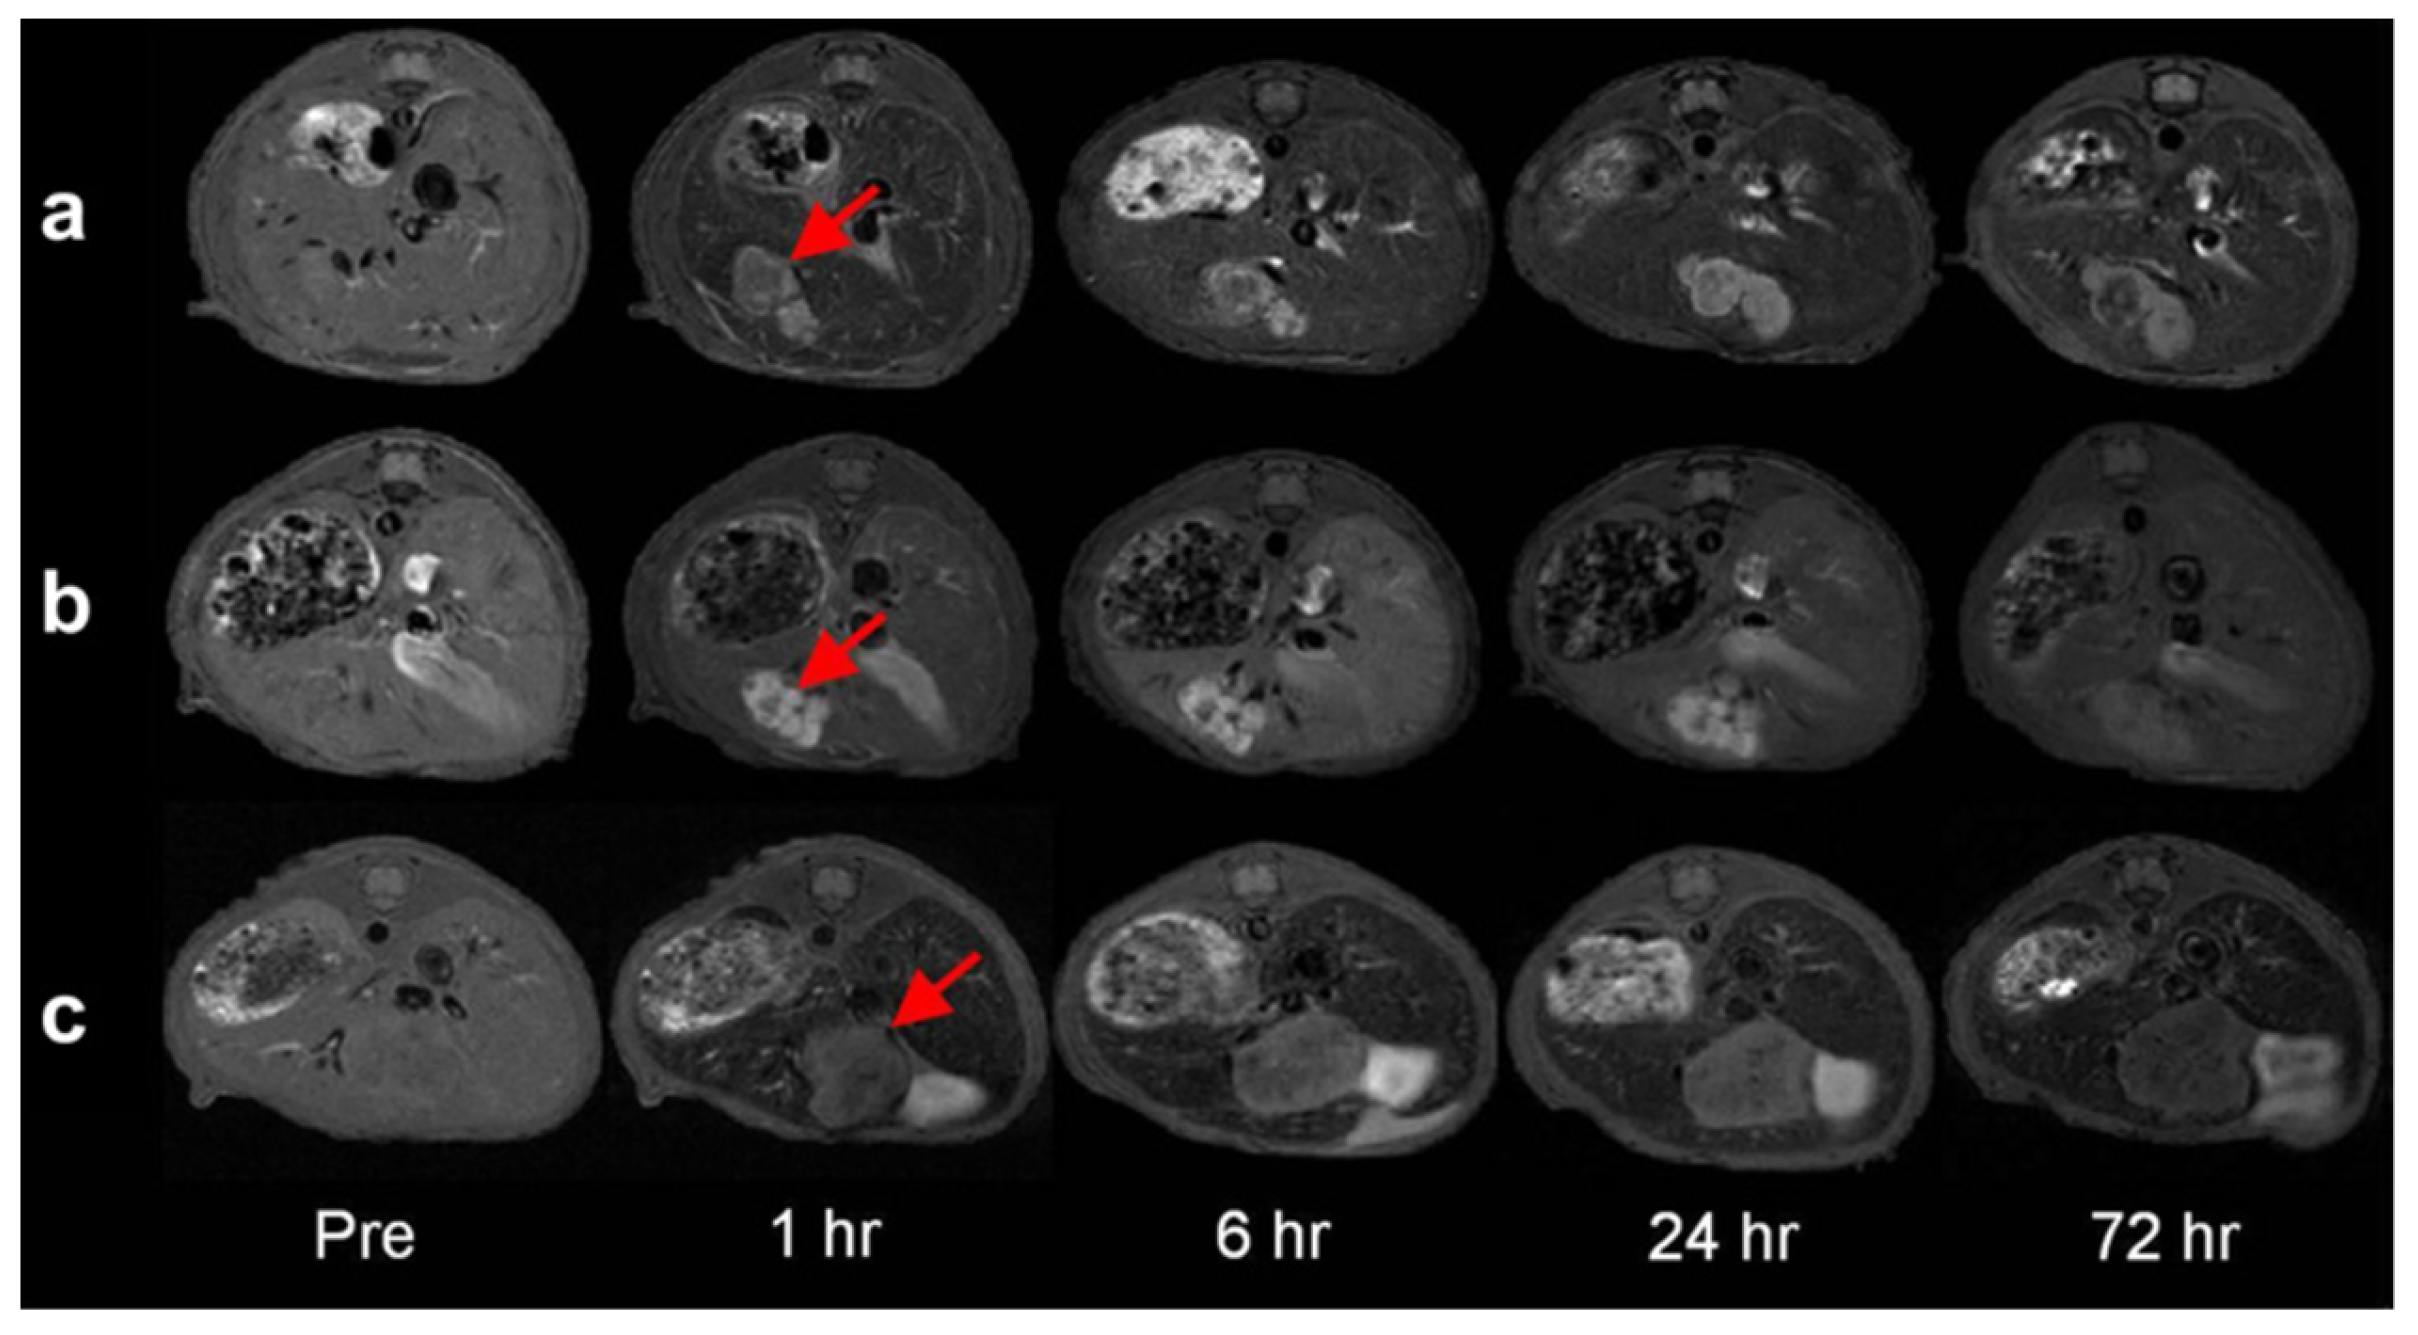

- Li, F.; Liang, Z.; Liu, J.; Sun, J.; Hu, X.; Zhao, M.; Liu, J.; Bai, R.; Kim, D.; Sun, X.; et al. Dynamically Reversible Iron Oxide Nanoparticle Assemblies for Targeted Amplification of T1-Weighted Magnetic Resonance Imaging of Tumors. Nano Lett. 2019, 19, 4213–4220. [Google Scholar] [CrossRef]